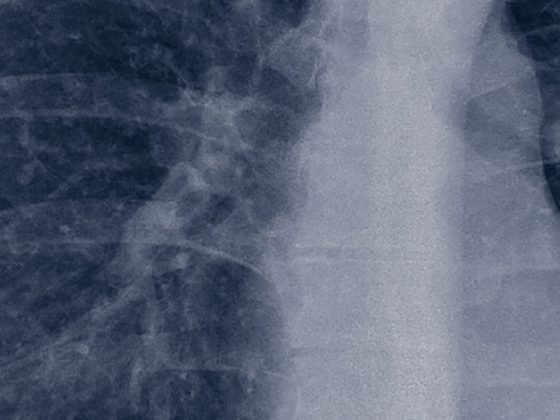

• Nicht-kleinzelliges Lungenkarzinom

Molekulare Diagnostik unter der Lupe

Bisher ist die molekulare Testung beim nicht-kleinzelligen Lungenkarzinom (NSCLC) vor allem Patienten im Stadium IV vorbehalten. Mit der Einführungzielgerichteter Therapien auch in früheren Tumorstadien könnte sich dies jedoch schon bald ändern – eine grosse Chance, die jedoch auch jede Menge Herausforderungen für den klinischen Alltag birgt.